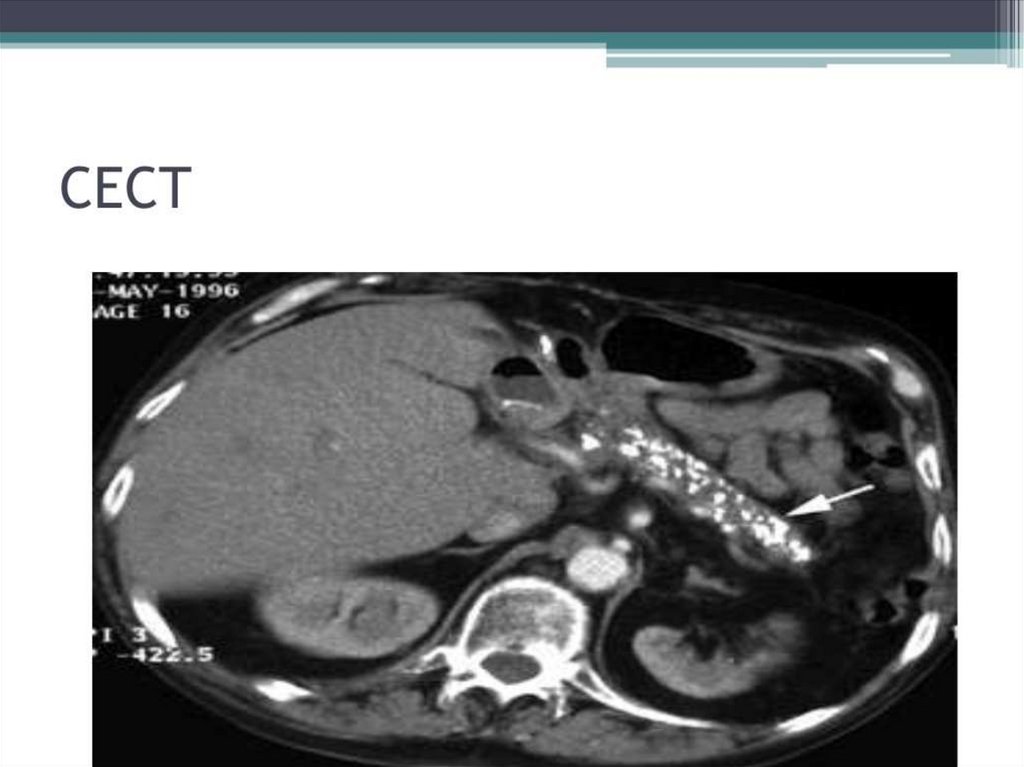

Chronic pancreatitis